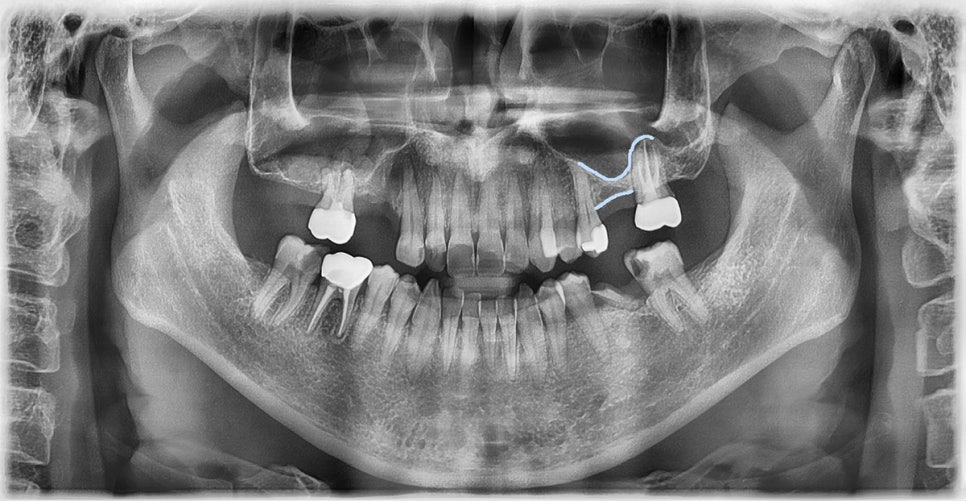

위 어금니가 빠져서 임플란트를 상담하러 오신 환자분들께 임플란트 수술을 하는 부위에 다른 수술도 함께 해야 한다고 설명드리는 경우가 종종 있습니다. 이 때 환자분들께 설명드리는 용어 중 하나가 바로 '상악동' 입니다. 상악동이란 위턱뼈 안에 있는 피라미드 모양의 빈 공간으로, 공기가 차 있는 주머니라고 생각하면 이해하기가 쉽습니다. 많은 분들께서 예전에 비해 임플란트 가격이 많이 내려가서 병원에서 일부러 이런 수술을 같이 권하는 것 아니냐고 오해하시는 경우도 간혹 있습니다. 그래서 이번 포스팅에서는 상악동이란 무엇이며, 어떤 경우에 꼭 해야 하는지에 대하여 설명드리고자 합니다.

얼굴의 코 옆, 볼 부위에 위치한 공기 주머니로, 우리 몸의 부비동 중 하나입니다. 이 공간은 코와 직접 연결되어 있으며, 호흡 과정에서 공기의 흐름을 돕고, 목소리의 울림을 조절하는 등 여러 가지 기능을 합니다. 또한 상악동의 안쪽벽은 점액막으로 덮여 있어, 세균과 같은 외부 물질을 걸러내는 역할도 합니다. 개인에 따라 상악동의 크기와 모양은 다양합니다.

상악동과 위 어금니 뿌리와의 위치관계

이와 같이 상악동은 우리 몸에서 중요한 역할을 하는 부분이기 때문에, 위 어금니 부위에 임플란트를 심게 될 때에도 공기주머니가 다치지 않도록 최대한 조심해야 하기 때문에, 위턱 잇몸뼈가 부족하여 상악동과의 거리가 가까울 경우 임플란트를 심는 것은 매우 난이도가 높은 시술이라고 할 수 있습니다.